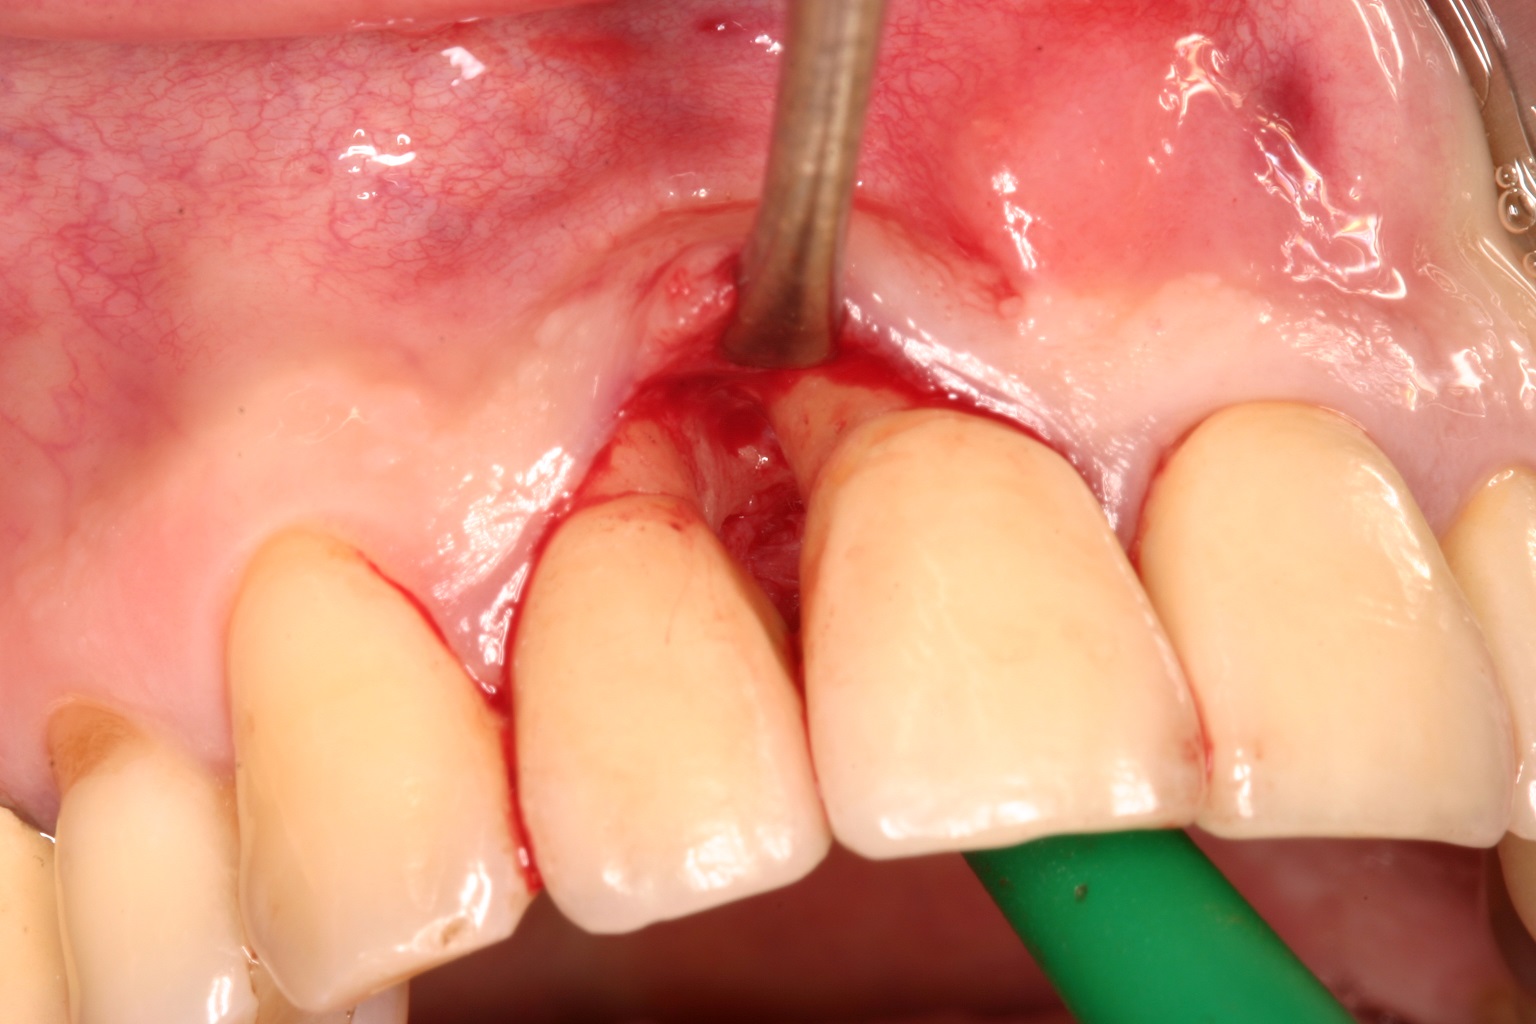

03/08 - Minimal buccal flap reflection according to simplified papilla preservation flap technique (Cortellini et al. Int J Periodontics Restorative Dent. 1999). The intra-operative view shows a deep intrabony defect distal on tooth 11.Non-contained intrabony defect treated with the simplified papilla preservation flap in conjunction with Straumann® Emdogain® and a particulate bone grafting material - Prof. Dr. Dr. A. Kasaj